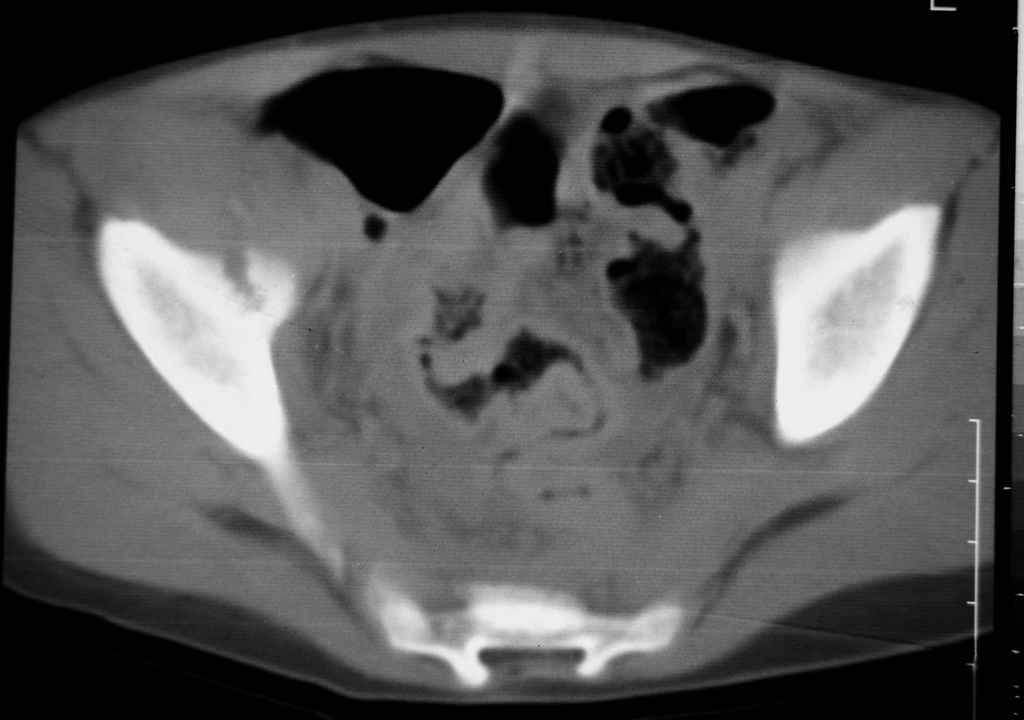

Перелом вертлужной впадины

Уважаемые коллеги, помогите определиться с тактикой лечения.Ребёнок 7 лет, травма 11.09.08, поступил с травматическим вывихом бедренной кости.

Вывих вправлен, конечность фиксирована на скелетном вытяжении. Что делать с переломом подвздошной кости? Лечить консерватино или оперировать?